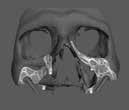

10.00–12.30 Dr. Mile Churlinov (Észak-Macedónia): Navigált fog autotranszplantáció „A fogvesztés általában parodontális patológiát, függőleges gyökértörést, szuvas destrukciót és traumát követően következik be. A fogak autotranszplantációja olyan technika, amely magában foglalja egy mesterséges fogágy sebészi létrehozását vagy frissen kihúzott fogazat felhasználását, és egy autogén kitört vagy kitöredezett fog újrapozicionálását a fogazat elsődleges szerepének helyreállítása érdekében a funkció, a beszéd és az esztétika szempontjából. (1,2) Míg a donorfog „”PDL”” megőrzése a siker kulcstényezőjének tűnik, (4,5) egyes kutatók úgy találták, hogy az éretlen fogaknak jobb a prognózisa autotranszplantáció esetén, mivel könnyebben elősegíthetik a revascularizációt, mint az érett fogak (3), több esetismertető tanulmány is magas sikerességi arányról számolt be az érett fogak autotranszplantációja esetén (6-8), és 98,0% és 90,5% 1 és 5 év alatt, a szisztematikus áttekintések szerint (6). Korábbi kutatók megállapították, hogy egy nyomtatott donorfog (3D replika) a foghúzás előtt optimalizálhatja az eljárás teljes idejét, és ami a legfontosabb, csökkentheti a donorfog extraorális idejét (9). A digitális tervezéssel és a CBCT-vel a frissen kihúzott fogazat már nem jelent korlátot, ha az egész eljárást jól megtervezték, és az eljárást gyorsan végzik (12). Anssari Moin és munkatársai leírták a számítógépes sablonvezérelt autotranszplantáció módszerét egyedi, 3D-ben tervezett/nyomtatott sebészi eszközökkel (13), néhány évvel később pedig Abella és munkatársai még tovább mentek egy egyedi tervezésű oszteotómmal és a donorfog teljesen feltárt bukkális falával (14). Ebben az előadásban a szerző bemutatja, hogyan lehet a modern technológia segítségével autotranszplantációt tervezni és végrehajtani különböző klinikai helyzetekben, és hogyan lehet azt a szakirodalom által is alátámasztani. A véletlen fogvesztés gyakoribb a fiatalabbaknál, mint a felnőtteknél. A hiányzó fog/fogak implantátummal történő kezelése felnőtteknél kiváló és kiszámítható módszer, de ellenjavallt növekvő egyéneknél, mivel nem biztosítja az alveoláris gerinc további növekedését függőlegesen, ahogyan a természetes fogazat hajlamos erre. A növésben lévő páciensek hiányzó metszőfogaival kapcsolatos követéses vizsgálatok azt mutatták, hogy hosszú távon a protetikai rehabilitáció volt a legkevésbé kívánatos kezelési lehetőség a fogszabályozással és az autotranszplantációval szemben. A sikeres implantációs eljárás elvégzése károsodott fogüreg esetén még legtapasztaltabb klinikusok számára is nagy kihívást jelentő feladat, illetve felnőtteknél jelentős csontveszteséggel és/vagy sinuslift beavatkozással jár. A rendelkezésre álló friss üreg vagy csontmagasság/szélesség gyors és kiszámíthatóvá teszi az eljárást. Másrészt, ha lágy- és keményszövethiány van, az autotranszplantáció előnyös lehet az implantátumokkal szemben, főként a „”PDL ‚’ csontinduktív potenciál és a lágyszövetekkel való optimális biológiai kölcsönhatás miatt.